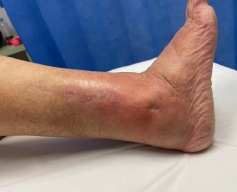

Ankle dislocation

Reduction under conscious sedation

- protects skin medially

- conscious sedation in emergency department

- well moulded cast

- unstable ankles need monitoring for loss of reduction

- can need external fixation to maintain position

Dislocationdislocationdislocation